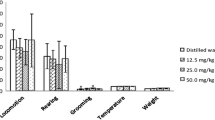

Summary of percentage effects

The results of all the experiments were pooled after standardizing the values for each mouse with respect to the mean value for the control mice of that experiment. The differences between each control vehicle-treated mouse, relative to the mean value of all the controls in the same experiment, were also computed. This made it possible to evaluate the variation between the two control groups and the stability of the system. A summary of the main results of this investigation is provided in Fig. 2. The mean percentage effect value for all the mice in the treated groups clearly shows a small increase due to G. sempervirens dilutions in the OF paradigm (panels A and B). In the OF, the G. sempervirens-treated animals (5C, 7C, 9C and 30C) exhibited 10–20% higher activity than the control. However, due to inter-individual variability of responses, these effects did not attain statistical significance in global ANOVA analysis. Buspirone had small, non-significant, effect on the amount of time spent in the center (panel A) and showed a tendency to inhibit the distance traveled in the center (panel B).

Effects of G. sempervirens dilutions and of buspirone on OF (a and b) and LD (c and d) behavioral parameters, expressed as percentages ± S.E.M. relative to the mean values for the vehicle-treated, control animals. N = 48 and 40 animals for G. sempervirens-treated and buspirone-treated groups, respectively. Global ANOVA values for these evaluations were: panel A for experiments df = 5, F = 0.97, p = 0.438; for groups df = 8, F = 1.89, p = 0.060; panel B for experiments df = 5, F = 2.72, p = 0.020; for groups df = 8, F = 1.39, p = 0.196; panel C for experiments df = 5, F = 2.51, p = 0.029; for groups df = 8, F = 3.11, p = 0.002; panel D for experiments df = 5, F = 2.97, p = 0.012, for groups df = 8, F = 3.35, p = 0.001. All interactions between groups and experiments were not significant. The p values (*p < 0.05; **p < 0.001) are from LSD-post hoc analysis by two-way ANOVA, comparing drug-treated groups or vehicle-treated groups (control groups A and B) with the mean of the corresponding control, vehicle-treated groups. LSD-post hoc analysis was not performed on data of panels A and B because global ANOVA was beneath the significance threshold

G. sempervirens treatment caused a markedly significant increase in the parameters of the LD paradigm (panels C and D). Here, the most active G. sempervirens solutions (5C, 9C and 30C) increased the parameters, considered to be a sign of reduced anxiety, by 20–40%. With respect to time spent in the light compartment, this effect was comparable to that of buspirone, while in terms of the number of transitions, the effect of G. sempervirens 9C and 30 C was much higher and more significant than that of buspirone. This was probably due to a sedative effect of buspirone which reduced the movement speed of the mice, an effect that was not observed using diazepam (1 mg/kg in acute treatment) in a separate experiment done under the same conditions (data not shown). The control groups A and B showed, in the various experimental models, a variability (positive and negative) relative to the mean that did not exceed 5%, tending to support the conclusion that the drug effects are real and not attributable to chance.